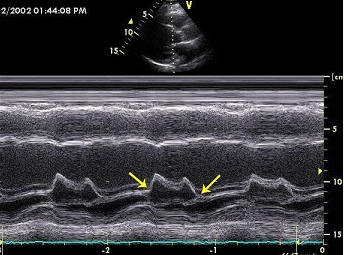

二尖瓣M型超声心动图,图中箭头所示两点称为()。

A . E点和A点